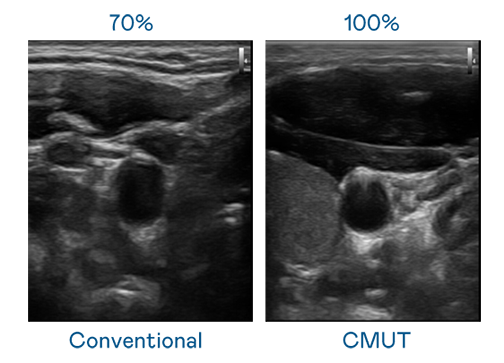

CMUT 技术是一种用电容式微机电元件来产生超音波讯号的技术。与传统 PZT 压电式技术相比,CMUT 频宽增加 30%,更宽频的超音波讯号让影像解析度大幅提升,是实现高影像品质医疗超音波扫描、促进精准医疗发展的关键技术。

大频宽带来超清晰影像

超音波影像的解析度高低,首先取决于探头能发出的讯号频宽。AG视讯 CMUT 可提供高清晰的超音波讯号,提供高频宽、高灵敏度、影像纹理细节更高的超音波影像,协助医护人员缩短影像判读时间及利用精准的医疗影像进行诊断。